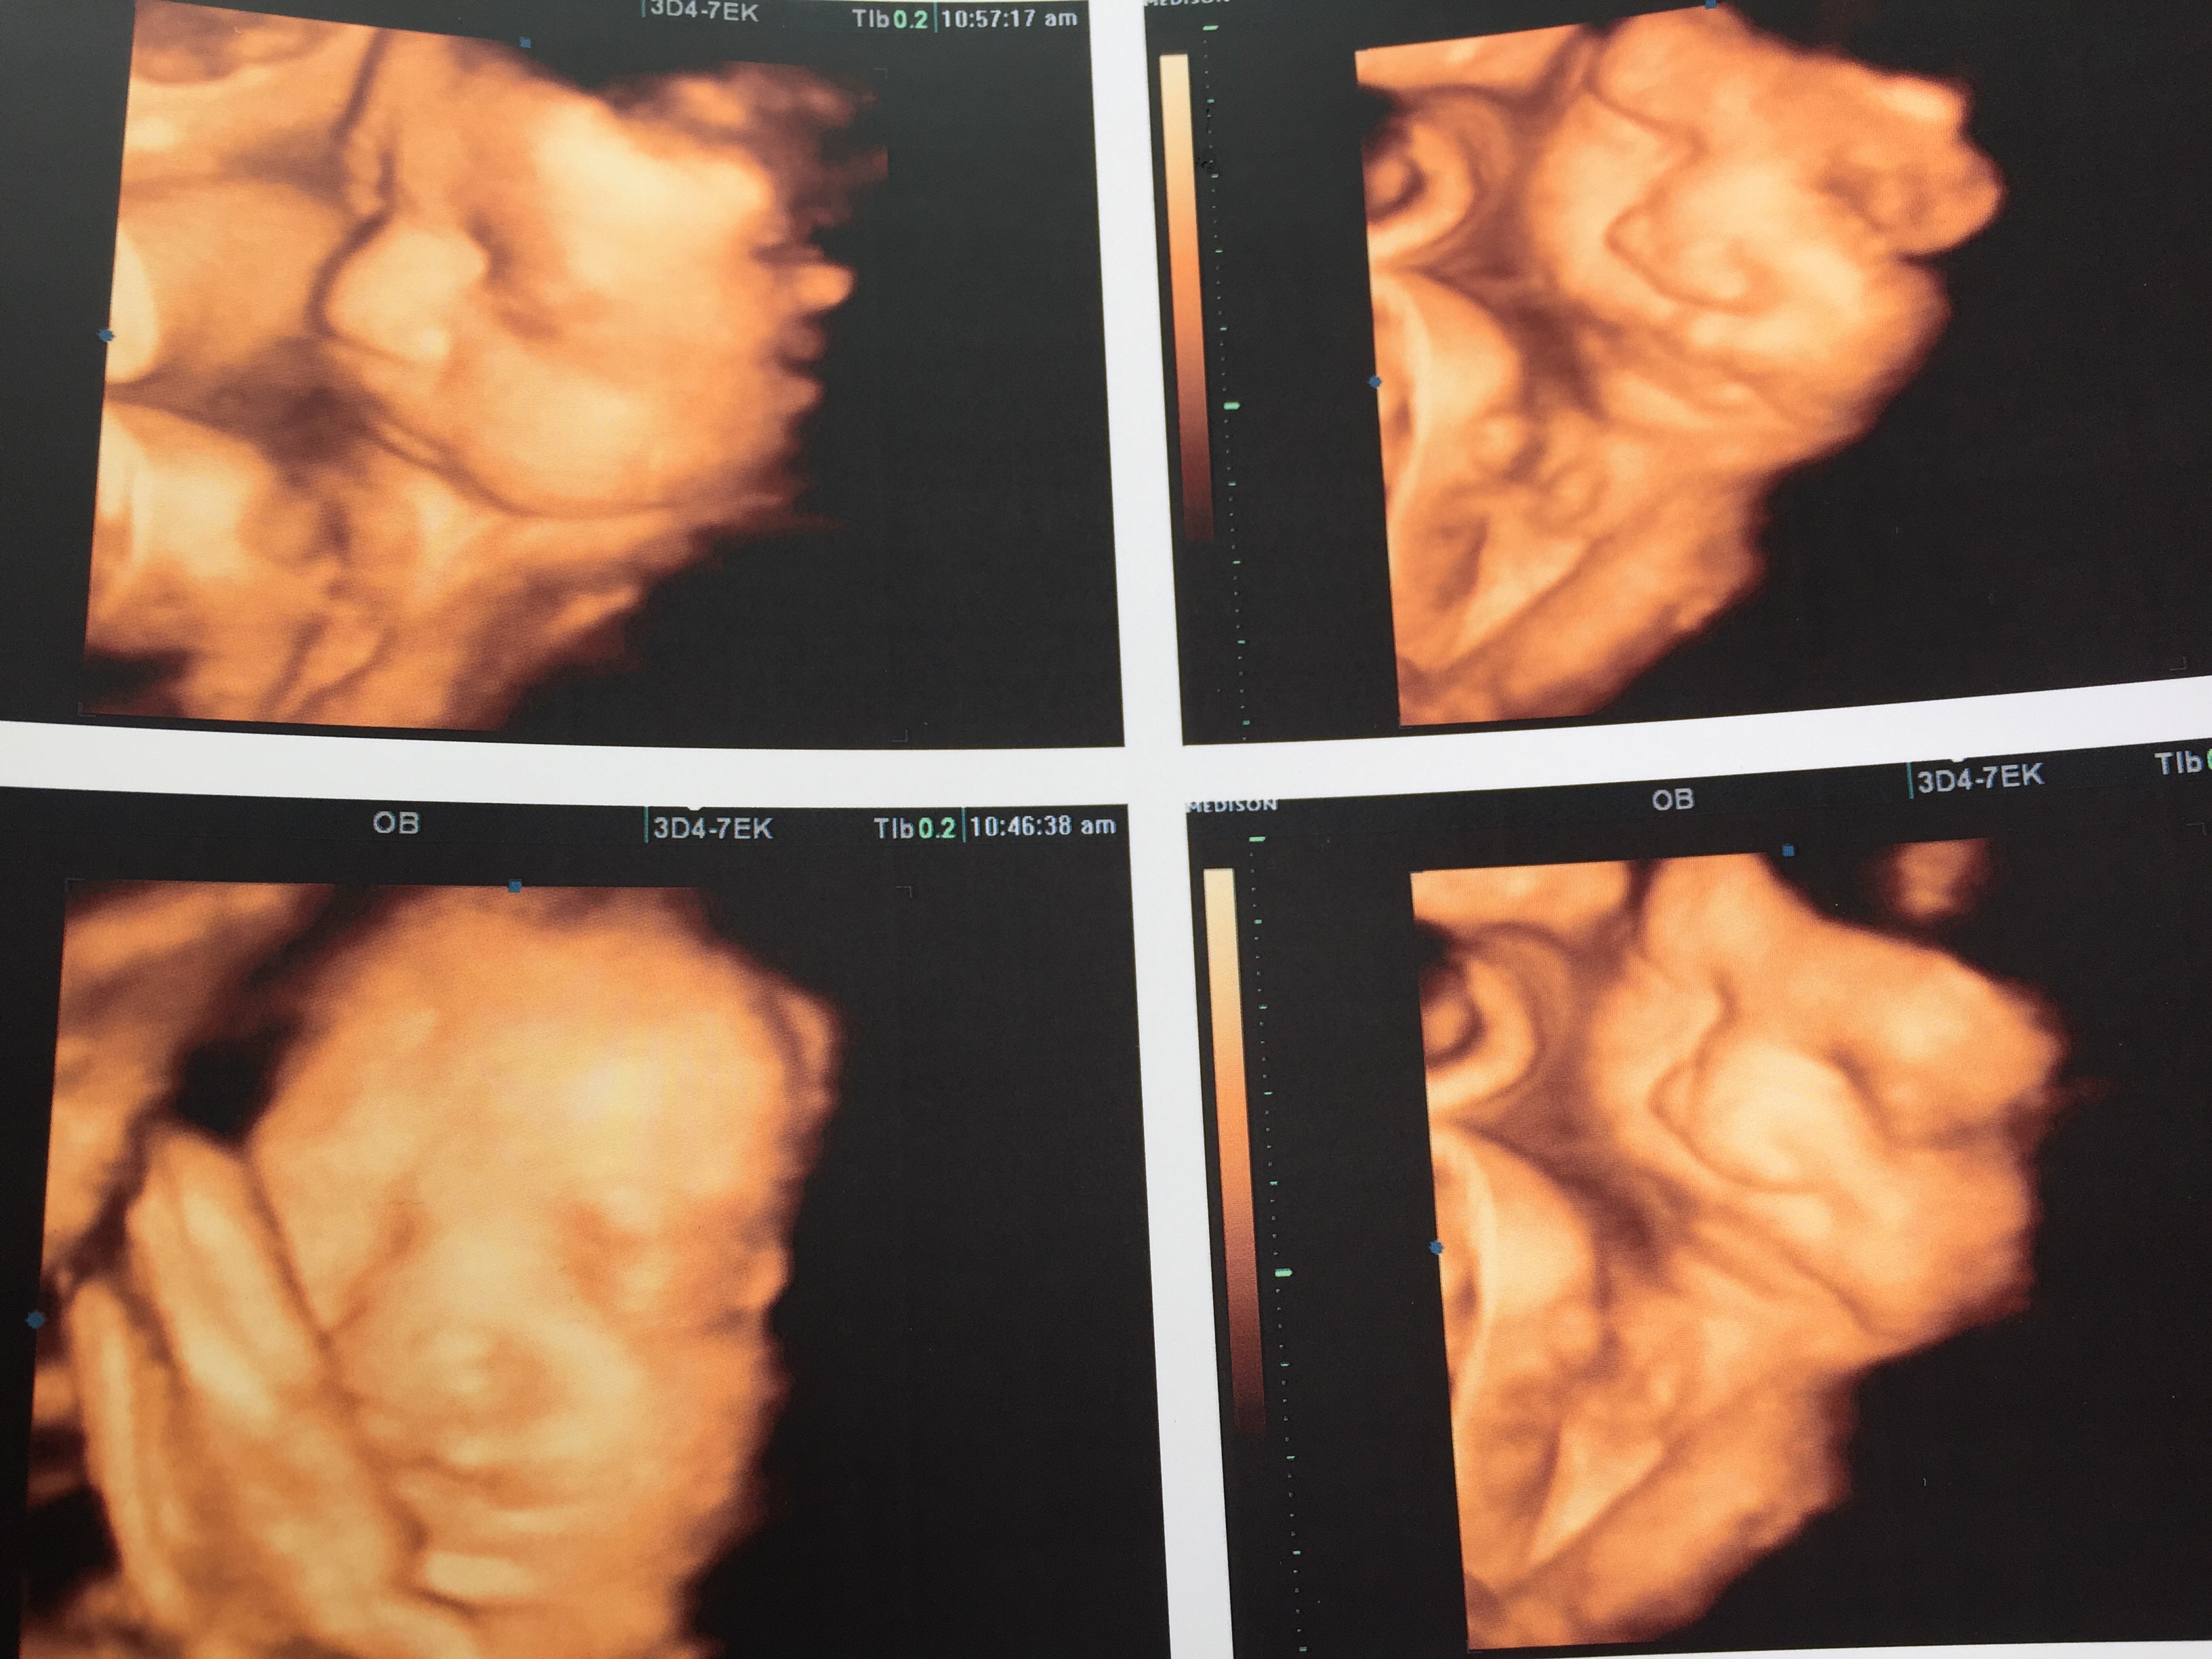

Who else got 4d I'd like to see pictures . Hoe far along were you and what was your experience.

Mine I was 33+4 weeks the experience was nice very large room and they had a large tv at the end of the room were you can see the video that way everybody won't be al over the tech besides the tech voice being really high pitched I enjoyed it lol and loved seeing my LO.

The second picture is my first born when he was 4 months and the bottom is the new addition :)